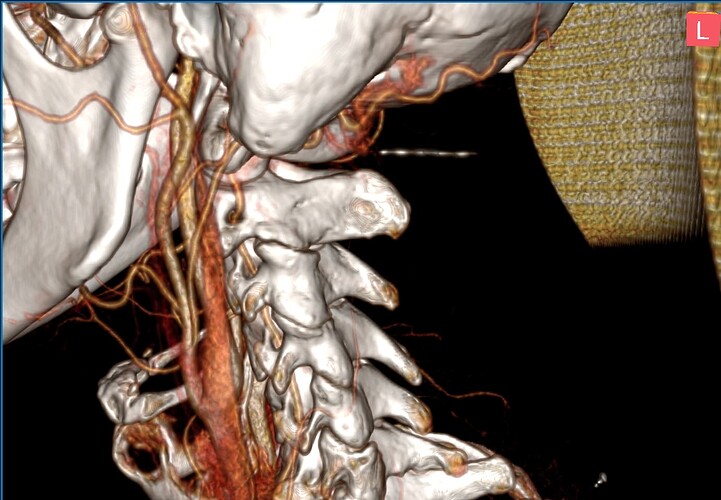

The distance between the styloid processes and the lateral masses of the C1 vertebra is 1.4 mm on the right and 2.2 mm on the left. The styloid processes are symmetrical and measure 25.5 mm in length.

Looked more into the hyoid bone piece that you pointed out @Isaiah_40_31 . It appears that the left greater horn is pressing into or resting on my carotid sinus on that side. Which is a bit alarming because of it’s role in blood pressure regulation and where vagus, and other nerves pass by. I’ve been to the ER a few times during this journey and all times my throat bone was at it’s sorest. My blood pressure was 155/106 upon admission and I wasn’t panicked or had any cognitive-driven anxiety, but definitely felt off. I wonder if the styloids/scm are culprits for pressure headaches, eye pain, tinnitis and dizziness, while the left greater horn is causing also dizziness/vertigo and vagus nerve and baroreceptor stuff (i.e., acid reflux, blood pressure and HR fluctuations, etc.)?

Then I found this lovely forum, where members seem to have a higher IQ (I actually test IQ frequently as a psychology student lol) than most of the doctors I’ve interacted with. You all have helped me narrow down my concerns and what things to hone in on – that being my styloids, hyoid, carotids, and jugulars. Based on our collective thoughts and what makes sense for what I’m experiencing, it appears that both IJVs are, to some degree, being compressed between my styloids and C1. It also appears that the left greater horn of my hyoid bone is pressed up against the area of my carotid sinus. I think a combination of these are contributing to my symptoms. We know IJV compression can cause some nasty symptoms, and I know based on research that pressure or irritation to the area of the carotid sinus can cause dizziness, weakness, and other pre-syncope symptoms that I experience with head movements and swallowing.

During my lengthy hikes I was carrying heavy backpacks. Seems irrelevant but I think that may have contributed to the hyoid bone piece. My neck curve may be exaggerated to a point from my sitting posture that my hyoid bone rests further back (i.e., my spine is drifting forward towards my hyoid around the level of c3-c4 ish). Or perhaps my greater horns are simply elongated. I think those long hikes with those heavy backpacks made the front of my throat taught (i.e., the skin and muscles) which pushed my hyoid back just the hair that was needed for significant enough compression on my carotids (which could have been building slowly for years). Looking back, my sleep was getting worse for about a year before my symptoms started and I was developing more and more brain frog and memory difficulties. I think the vascular ES piece (space between stlyoids and C1) was already in motion flying under the radar, and it wasn’t until my hyoid bone and carotid sinus problem and upper cervical neck cracking incident that brought the ES symptoms into light and more problematic.